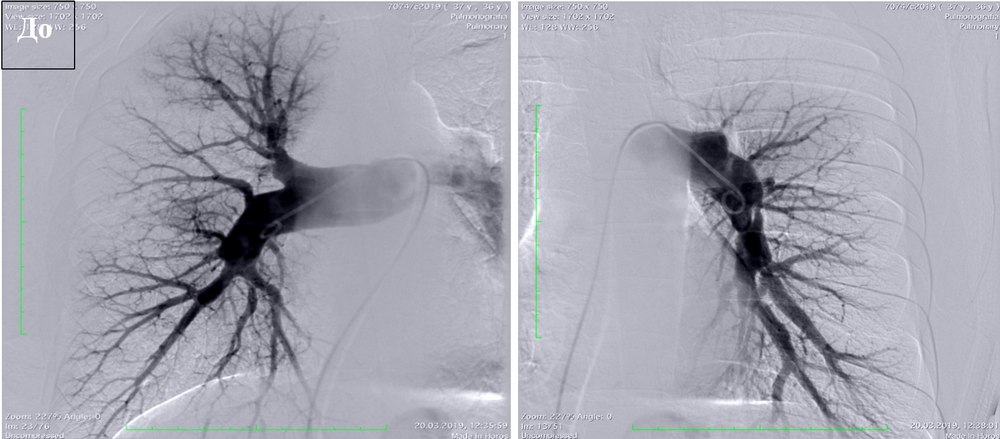

Сравнение данных ангиопульмонографии до и после операции (тромбэндартерэктомия из легочной артерии) |